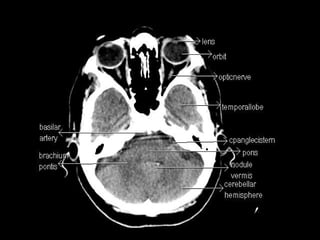

Radiographers use medical imaging equipment like X-rays and MRIs to produce images of patients' internal structures and organs. They are responsible for positioning patients, operating scanning machines, and ensuring quality images. Radiographers must have strong attention to detail, excellent communication skills, and the ability to work well under pressure to accurately capture anatomical features and diagnose any abnormalities.